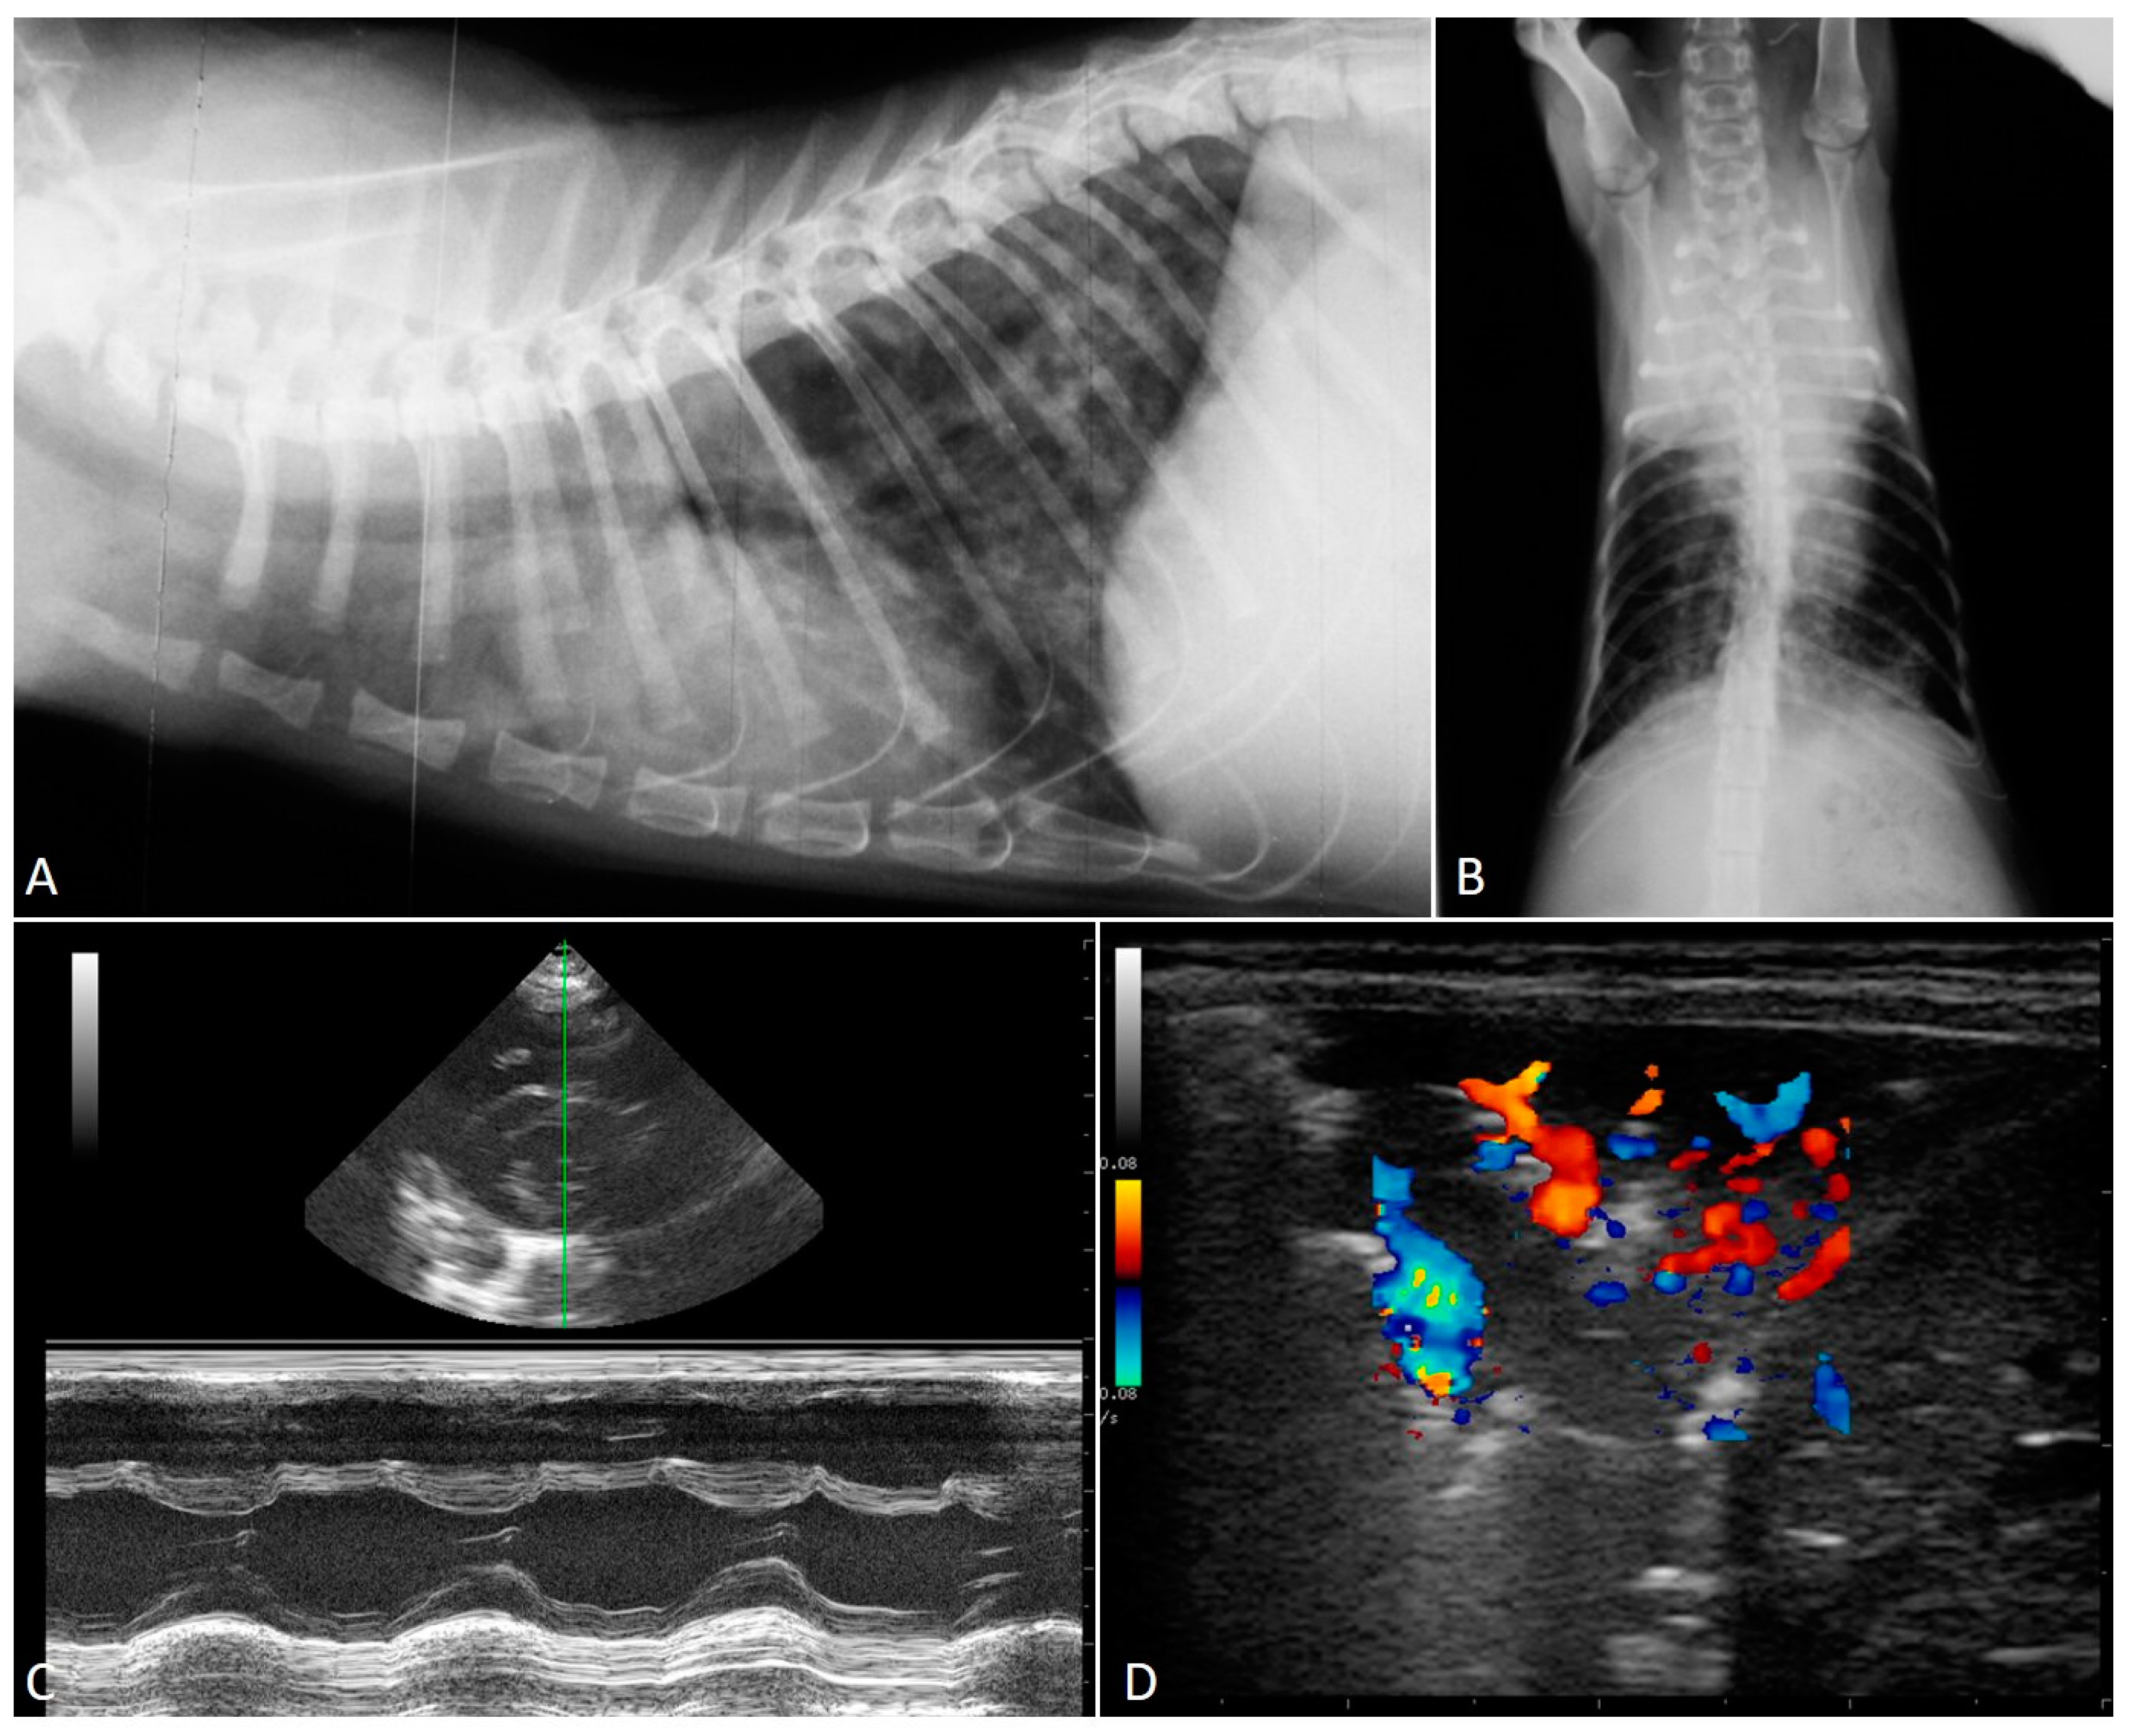

2.2. Radiographic Findings

2.3. Echocardiography

- Crisi, P.E.; Aste, G.; Traversa, D.; Di Cesare, A.; Febo, E.; Vignoli, M.; Santori, D.; Luciani, A.; Boari, A. Single and mixed feline lungworm infections: Clinical, radiographic and therapeutic features of 26 cases (2013-2015). J. Feline Med. Surg. 2017, 19, 1017–1029. [Google Scholar] [CrossRef] [PubMed]

- Febo, E.; Crisi, P.E.; Traversa, D.; Luciani, A.; Di Tommaso, M.; Pantaleo, S.; Santori, D.; Di Cesare, A.; Boari, A.; Terragni, R.; et al. Comparison of clinical and imaging findings in cats with single and mixed lungworm infection. J. Feline Med. Surg. 2019, 21, 581–589. [Google Scholar] [CrossRef]

- Genchi, M.; Ferrari, N.; Fonti, P.; De Francesco, I.; Piazza, C.; Viglietti, A. Relation between Aelurostrongylus abstrusus larvae excretion, respiratory and radiographic signs in naturally infected cats. Vet. Parasitol. 2014, 206, 182–187. [Google Scholar] [CrossRef]

- Lacava, G.; Zini, E.; Marchesotti, F.; Domenech, O.; Romano, F.; Manzocchi, S.; Venco, L.; Auriemma, E. Computed tomography, radiology and echocardiography in cats naturally infected with Aelurostrongylus abstrusus. J. Feline Med. Surg. 2017, 19, 446–453. [Google Scholar] [CrossRef]